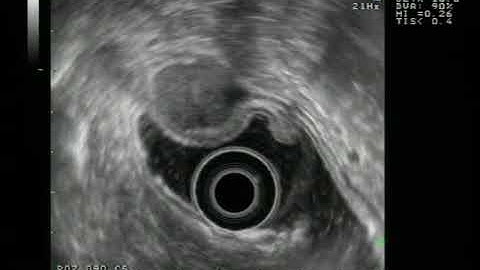

Malignant Gastric GIST